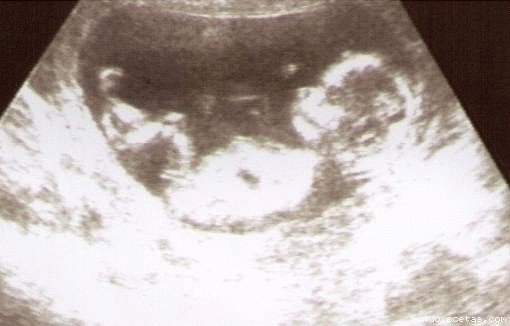

eco 13 semanas:

hola, el martes pasado mi hicieron esta eco, de 13 semanas,no la he puesto antes porque tenia el scaner fuera de uso y c**o me acaban de instalar un multifunci?n pues aprovecho y os la pongo

la verdad es que se ve estupendamente, le he visto las manitas con todos sus deditos, no paraba de moverse, se metía el dedo en la boca, pataleaba c**o un desesperado, parece increible que siendo tan pequeño ya se puedan distinguir hasta los deditos.